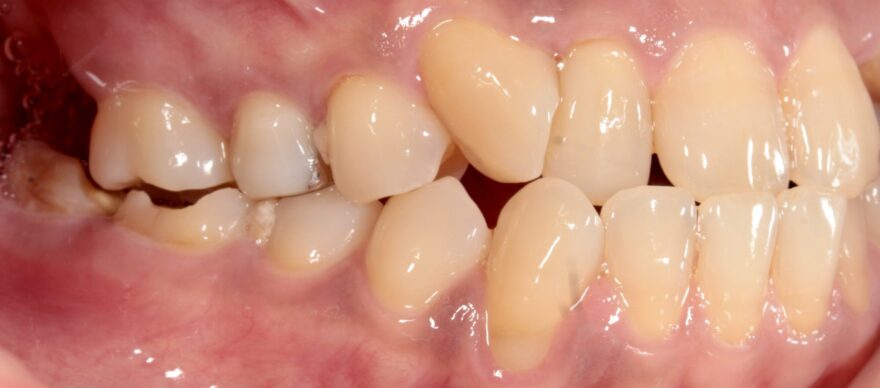

初診時の口腔内写真

左下の奥歯が崩壊しています。

右下の奥歯を失い、噛み合わせが歪んでいることが分かります。

右上の八重歯が気になります。

治療中の口腔内写真